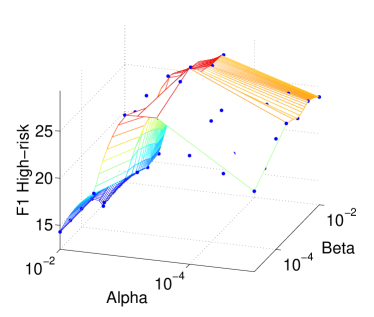

7.3.1 Sensitivity to Hyperparameters

There are two hyperparameters in our objective function in Eq. (8): the -norm regularization factor and the network regularization factor . These two factors serve different purposes: The -norm regularization as an embedded feature selection mechanism, and the network regularization for stabilizing the models. To investigate the sensitivity of the final performance against these hyperparameters, we perform a grid search in the set {,,,,,} for each. Figs. 4(a,b) report the -score measures for the moderate-risk ( class) and high-risk ( class) outcomes within months under cumulative classifiers (Section 5.1.1). The -scores in both risk classes critically depends on but are relatively stable against . The former dependency is expected: large generally leads to sparser models, and thus less overfitting. When the sparsity reaches the right level – at – the predictive power peaks. The small effect of on the performance is interesting but not surprising. As large forces linked features to have similar weights, the feature influence is rearranged but overall their total effect remains largely unchanged. Thus in what follows, unless specified otherwise, we fix the sparsity hyperparameter as for all classifiers.

Our work demonstrated that model stability for high-dimensional problems could be significantly enhanced by exploiting known relations between features. This validates our intuition that prior knowledge would help as it is independent of data sampling procedures. Consistent with prior studies, our results confirm that such prior relations, as realized in feature network regularization, improve the generalization when no other regularization schemes are in place [20][56]. However, interestingly, when combined with lasso, their effect on predictive performance is insignificant, as shown in Fig. 4. It is surprising because model stability could potentially lead to better prediction stability, and which is a sufficient condition for generalization [9, 49]. This suggests that the two stability concepts may not be strongly correlated, as it is known that random forests, for example, can generate very different tree ensembles (model instability) but the end results can be quite stable (prediction stability).